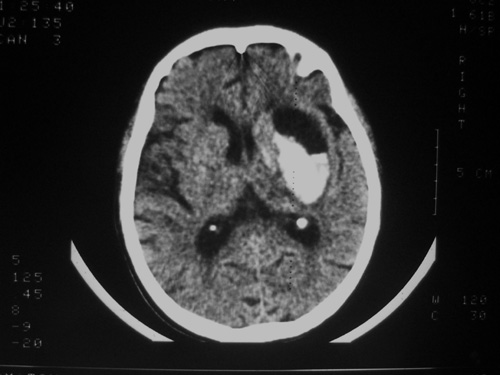

患者63岁,男。左侧肢体活动不灵一小时来诊。bp:175/75;家人否定有脑出血、脑梗死及其他病史。有嗜酒习惯。ct:右侧外囊区见不规则高密度影,边清,肯定是出血。可其周围低密度,边清,ct值与脑脊液相近,不像是水肿影,好似一软化灶形成。这种混合型病灶少见,请老师给予指导一下。

高密度灶为新鲜出血,临近低密度区为软化灶,可能为陈旧性梗塞或出血致。

首先考虑脑软化灶并出血。

囊性胶质瘤破裂出血不完全排除.

双侧额岛叶萎缩,病者有嗜酒习惯,考虑可能由酒精中毒引起的脑软化灶,合并脑出血,右基底节区亦有软化灶